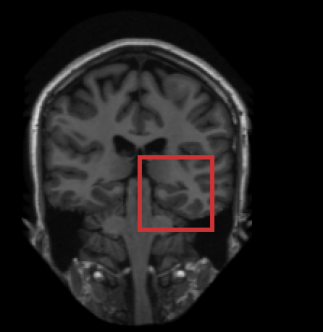

Fig. 2 shows the results of the described quantitative analysis, performed at intervals of 1000 mini-batches per task. As the networks learned, the obtained Dice coefficients increased and the stability of the results improved. For each segmentation task, the learning curves were similar for all experiments. Nevertheless, slight differences were visible between the obtained learning curves. To assess whether these differences were systematic or caused by the stochastic nature of CNN training, the training experiment using only brain MR data (Experiment 1) was repeated (dashed line in Fig. 2), showing similar inter-experiment variation. Fig. 3 shows a visual comparison of results obtained for the three different tasks. For all three tasks, all four networks were able to accurately segment the target tissues.

Including multiple tasks in the training procedure resulted in a segmentation performance equivalent to that of a network trained specifically for the task (Fig. 2). Similarities between the tasks, e.g. presence of the pectoral muscle in both breast MR and cardiac CTA, or similar appearance of brain and breast tissue in T1-weighted MRI, led to very limited confusion. In future work, we will further investigate the capacity of the current architecture with more data and segmentation tasks, and investigate to what extent the representations within the CNN are shared between tasks.